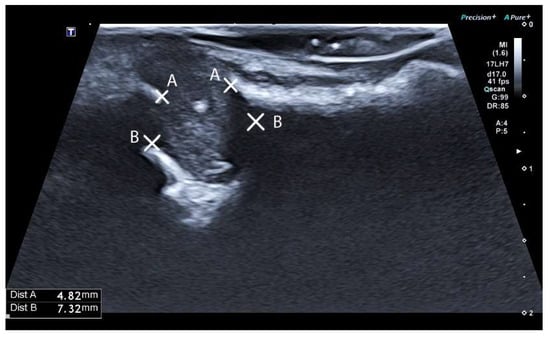

2.3.3. Ultrasound Examination and Evaluation